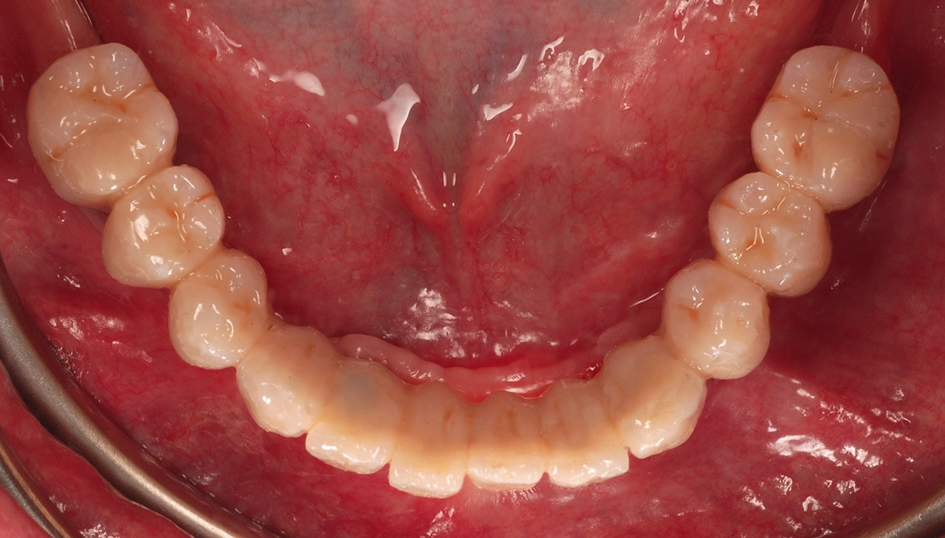

In unserem Patientenfall waren die Implantate annähernd parallel positioniert worden, so dass keine großen Abweichungen der Implantatachsen bestanden (Abb. 10). Es war ausreichend intermaxillärer Raum vorhanden und wir konnten den Patienten mit einer auf Kugelkopf-Attachments fixierten Unterkiefer-Cover denture Prothese versorgen. Das klinische Ergebnis war für Behandler und Patient gleichermaßen in optischer und funktioneller Hinsicht sehr zufriedenstellend (Abb. 11 und 12).